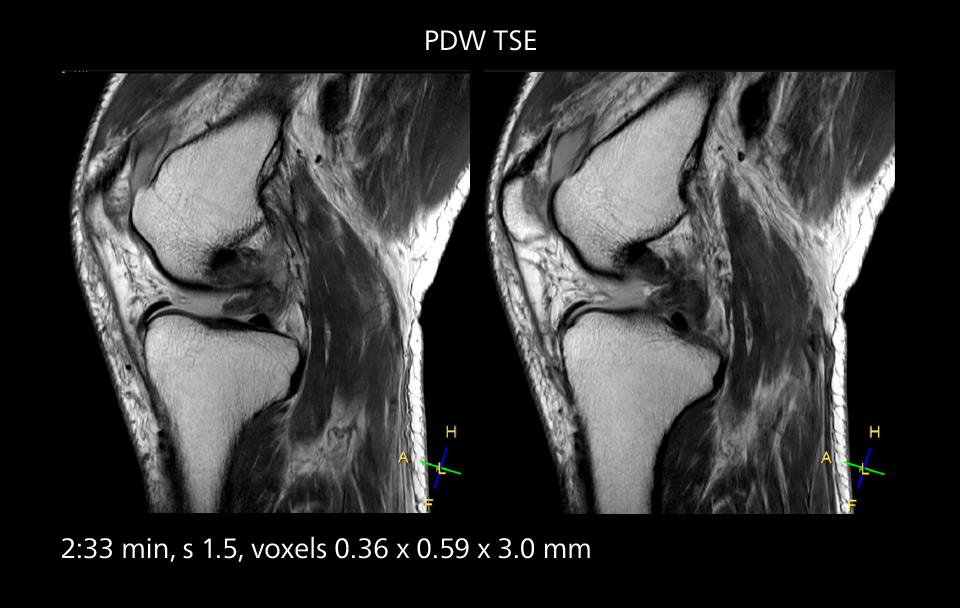

An example of increased imaging speed is in knee studies. “There is a definite scan time reduction for T2* mFFE and proton density TSE – both of these sequences benefit from much shorter repetition times,” he reports.

Images showing a posterior cruciate ligament (PCL) tear, a detached medial collateral ligament (MCL) on the tibial side and an intact anterior cruciate ligament (ACL). SmartPath to Elition X helped reduce scan time compared to previous imaging while maintaining resolution.

Overall, imaging time per sequence has been reduced since the Elition X upgrade. This can help reduce the risk of patient movement and the need for rescans.

“As our hospital has many elderly patients, we consider it important to obtain high-quality data in a short time,” Dr. Makuuchi says. “Shorter imaging times are also useful for accepting emergency patients, because faster emergency studies have a reduced impact on the daily examinations schedule. In emergency cases it is also important that high quality images are obtained in a short time.”